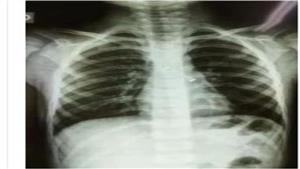

أشعة المرضى